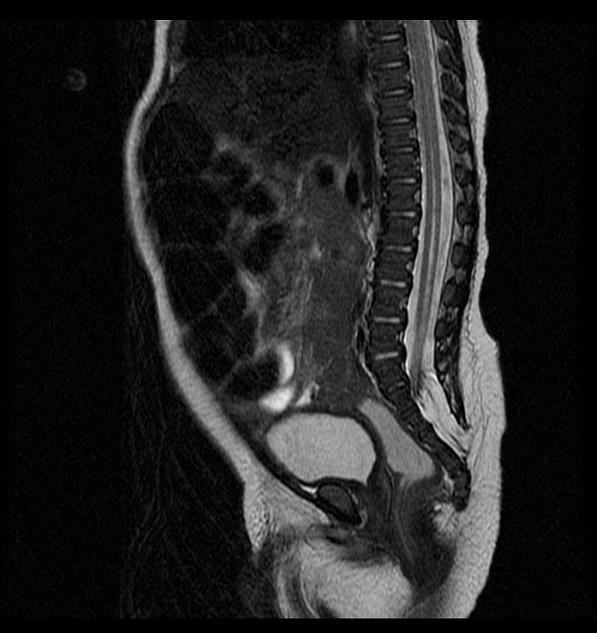

En nuestro paciente se solicita ecografía lumbosacra en que se detecta alteración anatómica. Requiere RM para confirmación. ¿Qué vemos en la prueba de imagen?: